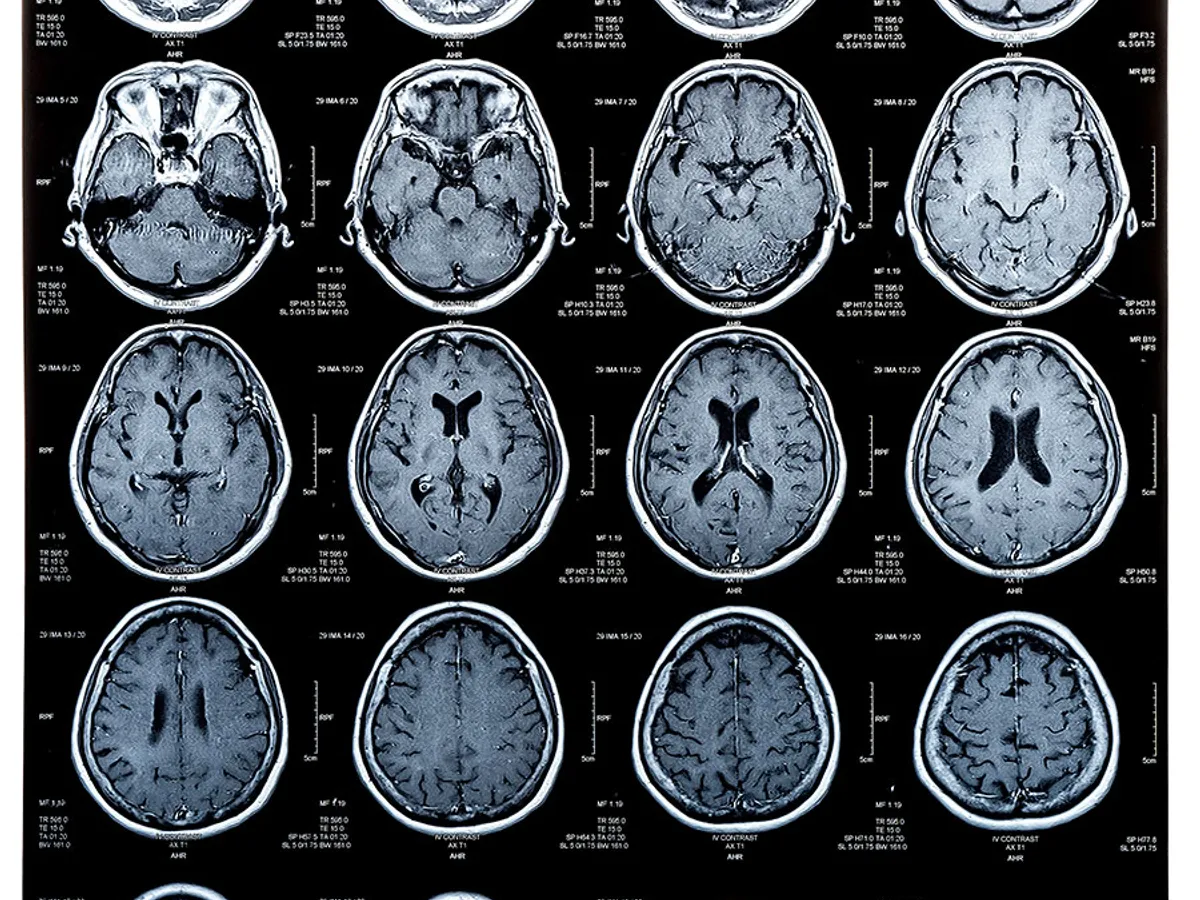

După o serie de eșecuri demoralizante, oamenii de știinţă care cercetează boala Alzheimer cred acum că sunt pe drumul cel bun pentru a oferi tratamente eficiente. Cât de curând vor fi ele disponibile?

Cel mai important, mulți oameni de știință cred că sunt în cele din urmă pe drumul cel bun.